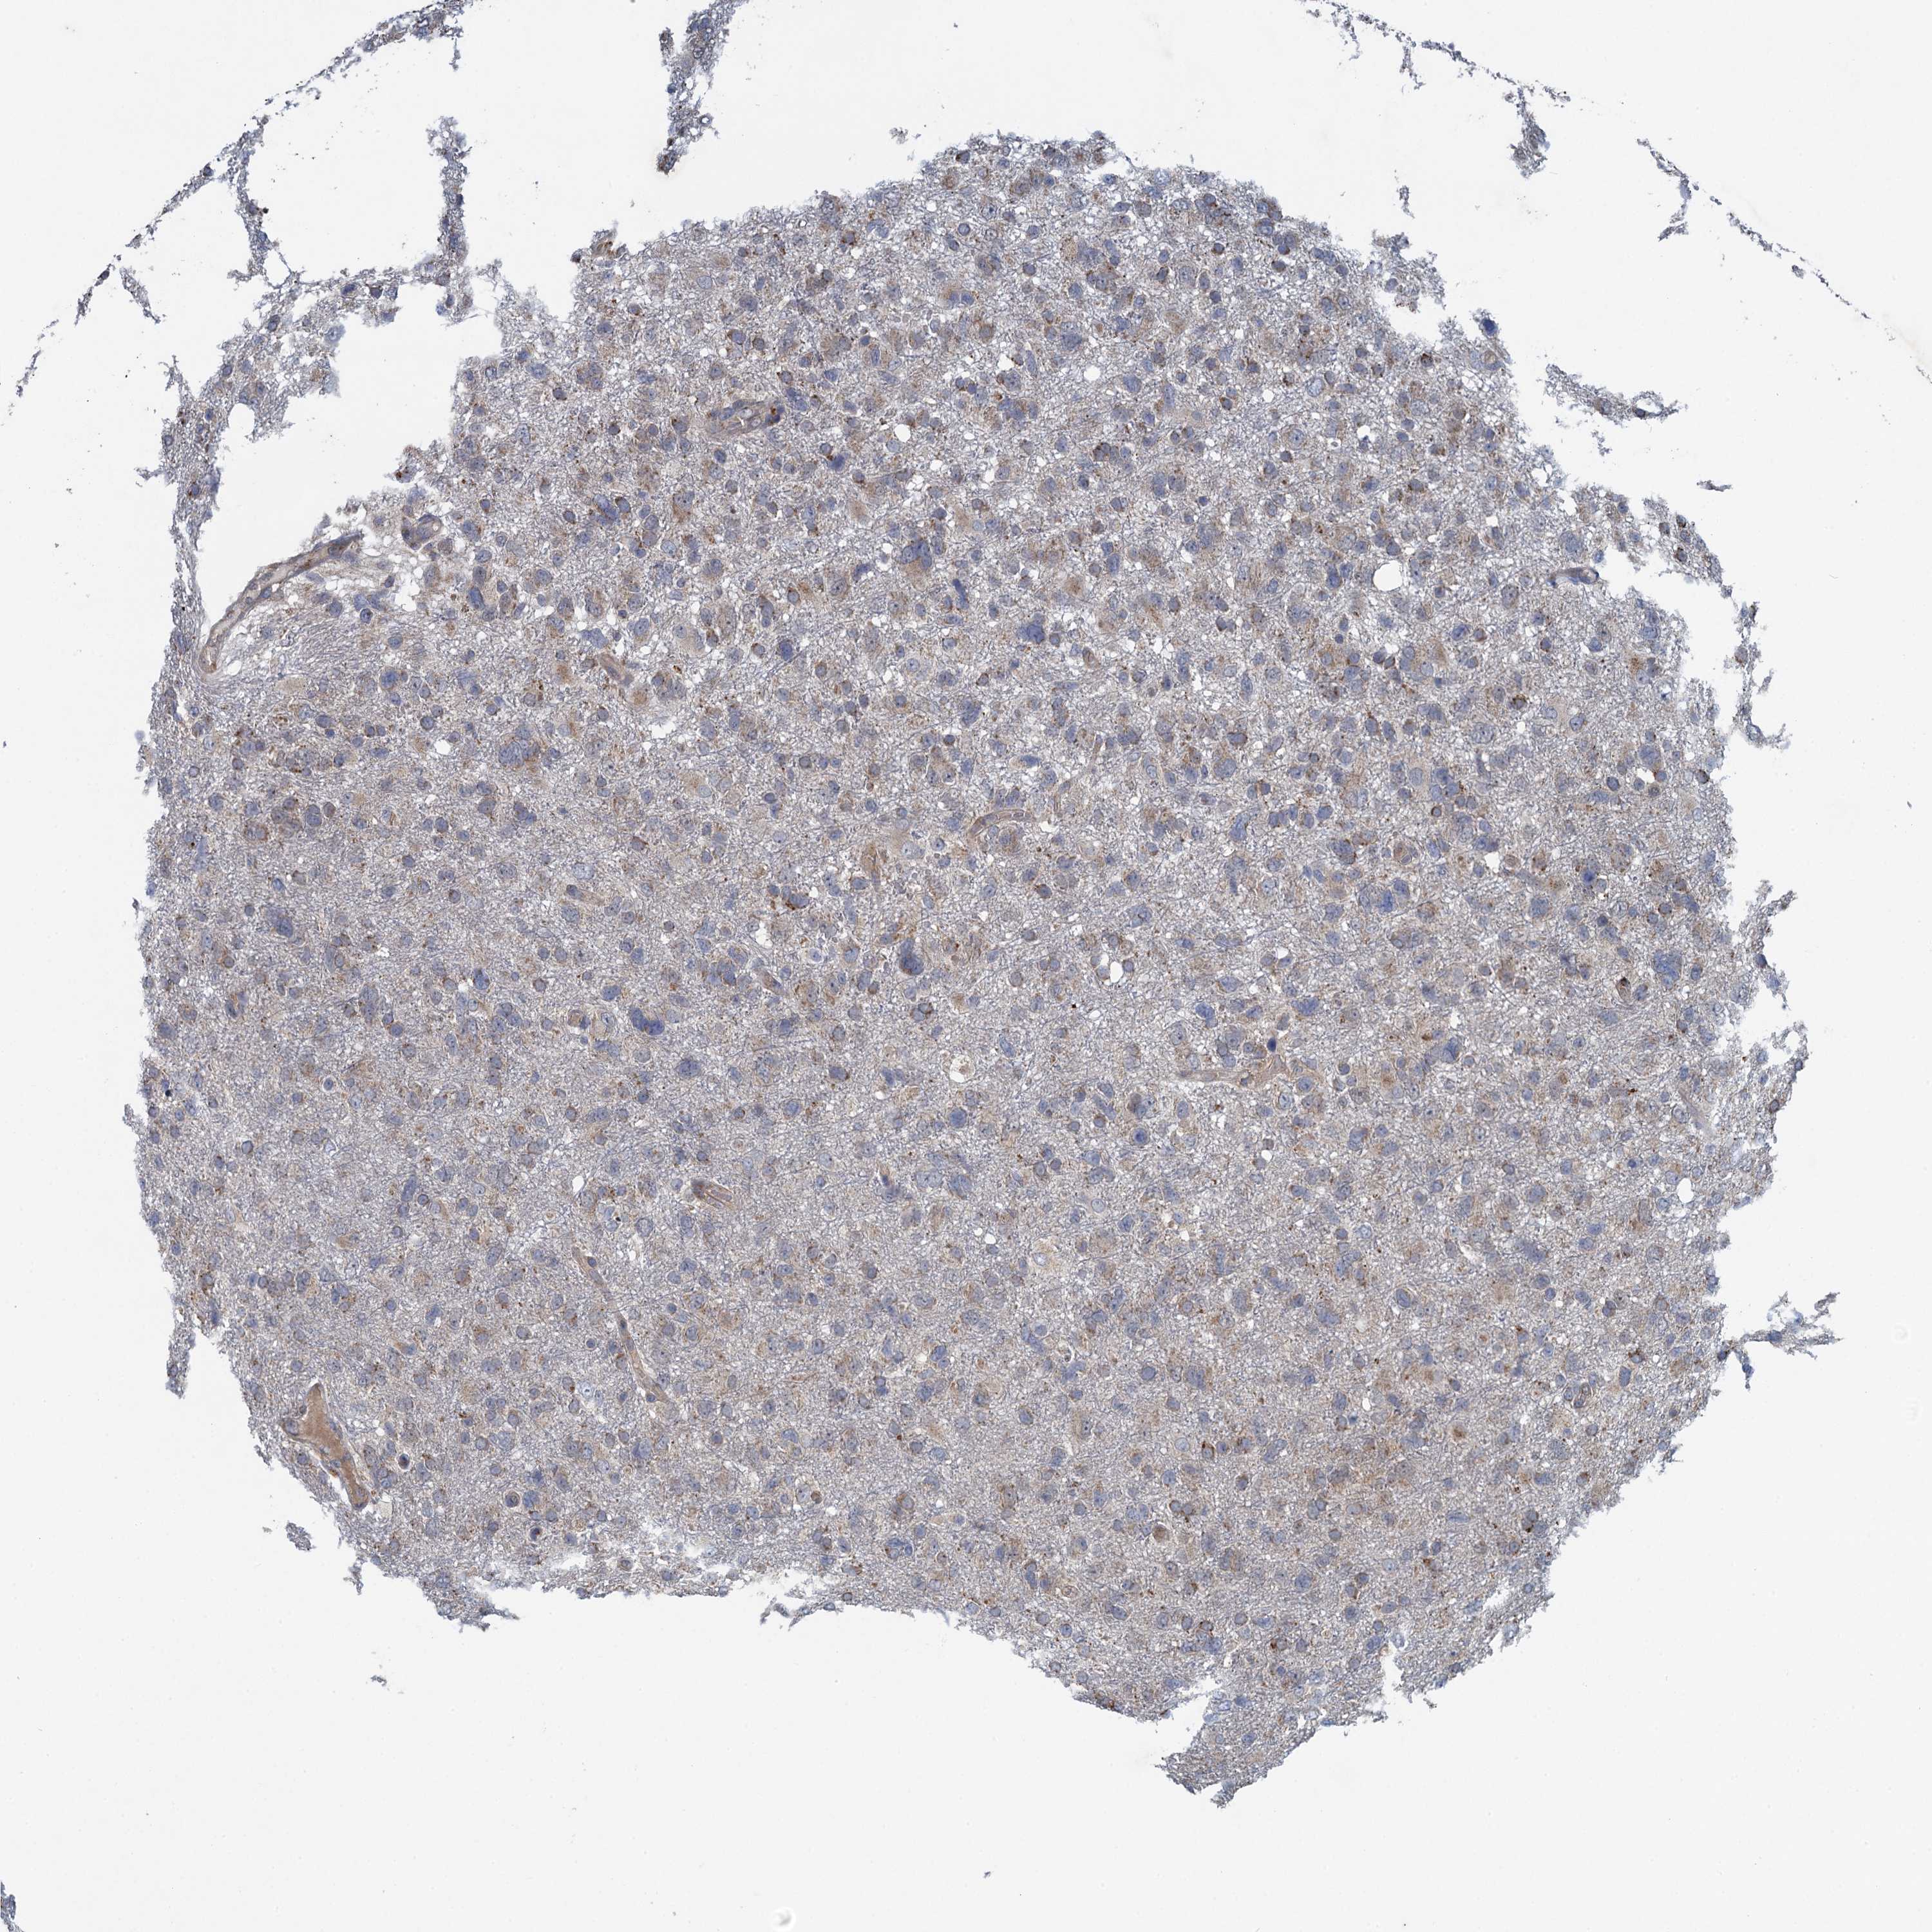

GLIOMA - Protein expressioni

A mouse-over function shows sample information and annotation data. Click on an image to view it in a full screen mode. Samples can be filtered based on level of antibody staining by selecting one or several of the following categories: high, medium, low and not detected. The assay and annotation is described here.

Note that samples used for immunohistochemistry by the Human Protein Atlas do not correspond to samples in the TCGA dataset.

Antibody stainingi

Antibody staining in the annotated cell types in the current human tissue is reported as not detected, low, medium, or high, based on conventional immunohistochemistry profiling in selected tissues. This score is based on the combination of the staining intensity and fraction of stained cells.

Each image is clickable and will lead to virtual microscopy that enables deeper exploration of all samples and also displays staining intensity scores, fraction scores and subcellular localization as well as patient and tissue information for each sample.

Antibody HPA041285

Antibody HPA069190

Staining

High

Medium

Low

Not detected

Intensity

Strong

Moderate

Weak

Negative

Quantity

>75%

75%-25%

<25%

None

Location

Nuclear

Cytoplasmic/membranous

Cytoplasmic/membranous,nuclear

Glioma, malignant, High grade

Glioma, malignant, Low grade